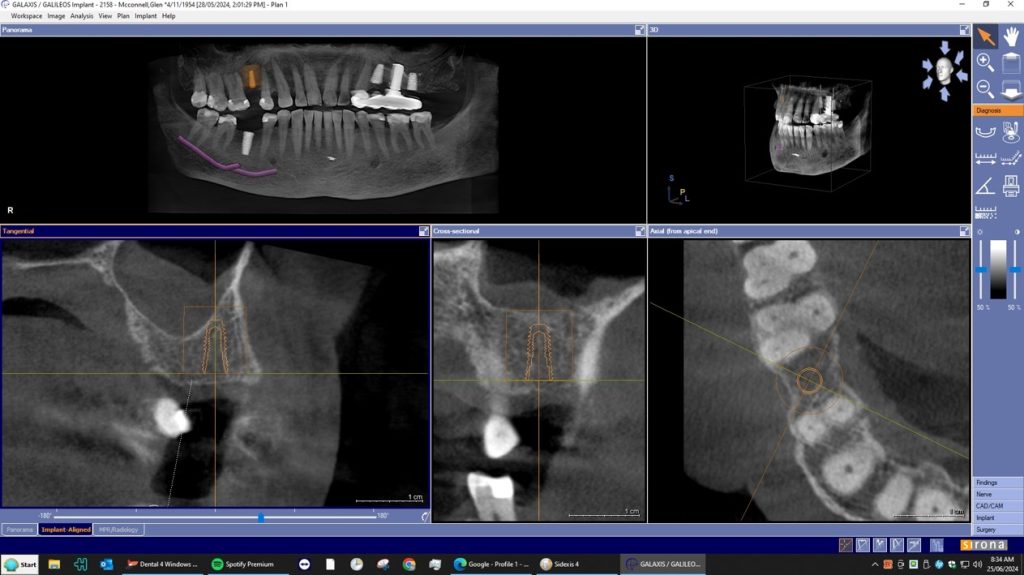

A dental Implant is a titanium “root” that integrates directly with the surrounding bone and replaces the function of the natural tooth. Neoss Implants are made using the best quality medical grade titanium, which is well known for its proven biocompatibility, and have a treated surface to facilitate bone integration.

The aim is to improve your health, chewing function and/or aesthetic appearance and once healing and restoration is complete you will be able to enjoy a wide variety of foods again.